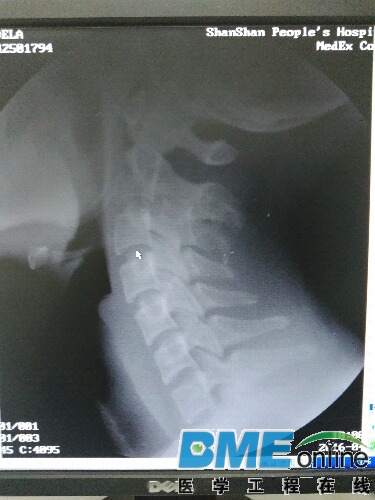

这是今天下午做的病人颈椎

我的工具包做的但是很清楚